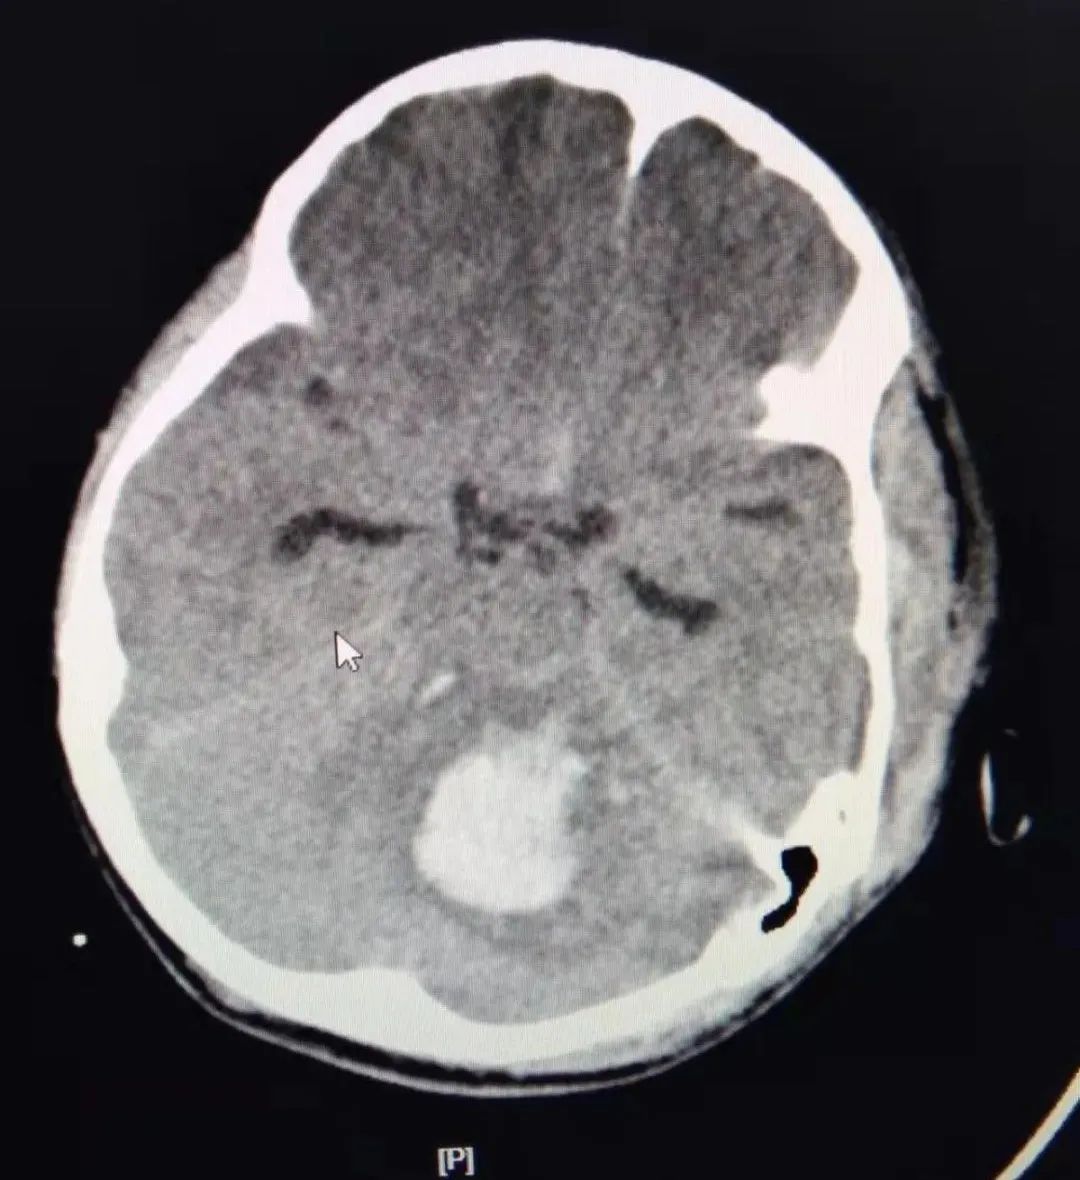

行相关检查,初步诊断:其意识丧失、呼吸循环衰竭,处于休克状态。CT显示严重多发脑挫裂伤、小脑出血,合并严重脾破裂、重度肺挫伤,胸腔、腹腔大量积血,肾挫伤、骨盆骨折。病情十分严重,生命危在旦夕!

术后发现由于小脑外伤性血肿进行性增多已达20毫升,严重脑水肿,脑干受压,随时有枕骨大孔疝发生和呼吸、心跳骤停的致命危险!

神外NSICU张国庆团队立即接棒进行微创手术清除脑内血肿,手术历经1小时后顺利完成。